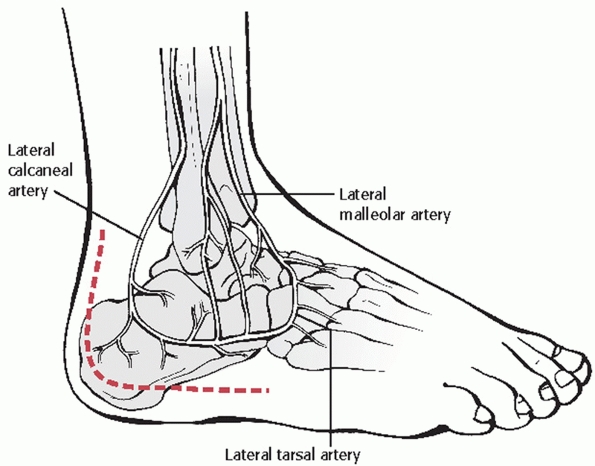

FIGURE 59-24

Lateral vascular anatomy. (Redrawn from Borrelli J Jr, Lashgari C. Vascularity of the lateral calcaneal flap: a cadaveric injection study. J Orthop Trauma 1999;13:73-77, with permission.) |

described the arterial blood supply of the subcutaneous tissues of the

(Fig. 59-24). Three arteries—the lateral

calcaneal, the lateral malleolar, and the lateral tarsal artery—were

consistently found along the lateral aspect of the hindfoot. The

lateral calcaneal artery appeared to be responsible for the majority of

the blood supply to the corner of the flap and, because of its

proximity to the vertical portion of the typical incision, it appeared

most likely to be injured from inaccurate placement of the incision. As

a result of this work, and to protect the sural nerve, the authors

recommended that the vertical limb of the incision be started just

anterior to the lateral edge of the Achilles tendon and at the crease

of the heel pad and lateral foot. This study therefore supports the

original description of Seligson.82